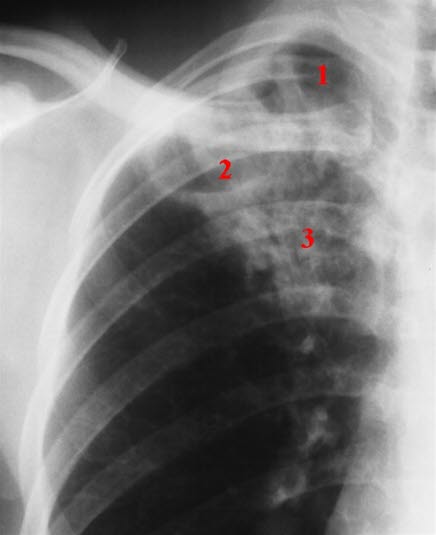

Lungetuberkulose er den viktigste tuberkuloseformen, og den eneste varianten av tuberkulose som er smittsom. Når det påvises en positiv blodtest (IGRA), tas det derfor alltid lungerøntgen etterpå for å bekrefte eller avkrefte om det foreligger aktiv lungetuberkulose.

Hvis lungerøntgen viser tegn til aktiv tuberkulose, må det gjøres direkte mikroskopi og tas dyrkningsprøver av oppspytt eller skyllevæske fra bronkiene. Pasienter med positiv mikroskopi er mer smittefarlige enn de med negativ mikroskopi. Resultat av direkte mikroskopi av oppspytt (ekspektorat) er avgjørende for å kunne vurdere smittsomhet. Dersom tuberkelbakteriene lar seg påvise ved mikroskopi, vil diagnosen være klar i løpet av få timer.